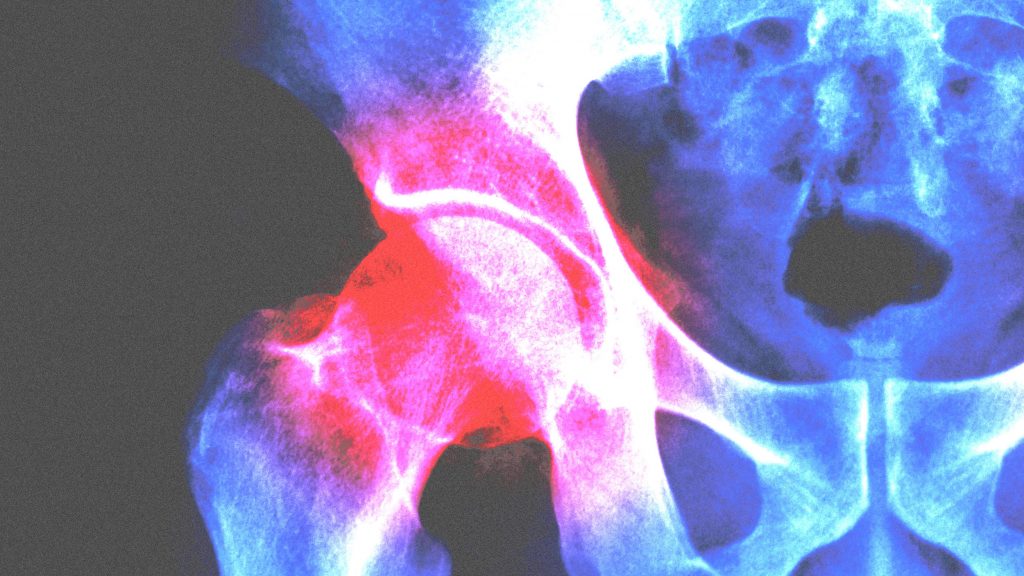

Ayurveda For Hip Joint Pain. Hip pain is the pain and. learn how to relieve joint pain naturally using ayurveda. Consult with durja ayurveda to get relief. These therapies balance the doshas, promote detoxification, and support the body’s natural healing mechanisms. To treat hip pain patient is. according to ayurveda, hip pain can be a symptom of kati shool, caused by vitiation of vata dosha. abhyanga (ayurvedic massage): Abhyanga is a traditional ayurvedic massage that helps improve blood circulation, reduce inflammation, and alleviate pain in the affected joints. hip pain caused by avn can be a debilitating condition, but there are many ayurvedic therapies that can help to. Explore these natural remedies, dietary changes, lifestyle changes and more to promote your joint health. Evaluating ayurveda’s effectiveness in alleviating hip pain from arthritis. Explore the potential of ayurvedic remedies in relieving hip. It can be tailored to focus on the areas affected by avn. ayurvedic therapies can be beneficial in managing osteoarthritis symptoms by reducing pain and inflammation and improving joint function. ayurvedic treatment for hip joint pain has effective results without any surgery to get rid of the pain naturally.